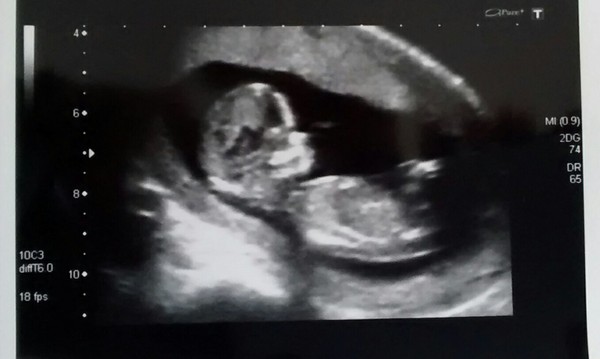

elio · 06/03/2015 07:47

Scan photo from yesterday, have really enjoyed seeing everyone elses, so thought I should add mine.

elio lovely pic! 11 days til my scan ahhhh

Lovely scan Elio!

aww lovely scan elio

Lovely elio :)

elio lovely scan!!

Lovely to see all the scan pictures so far :)